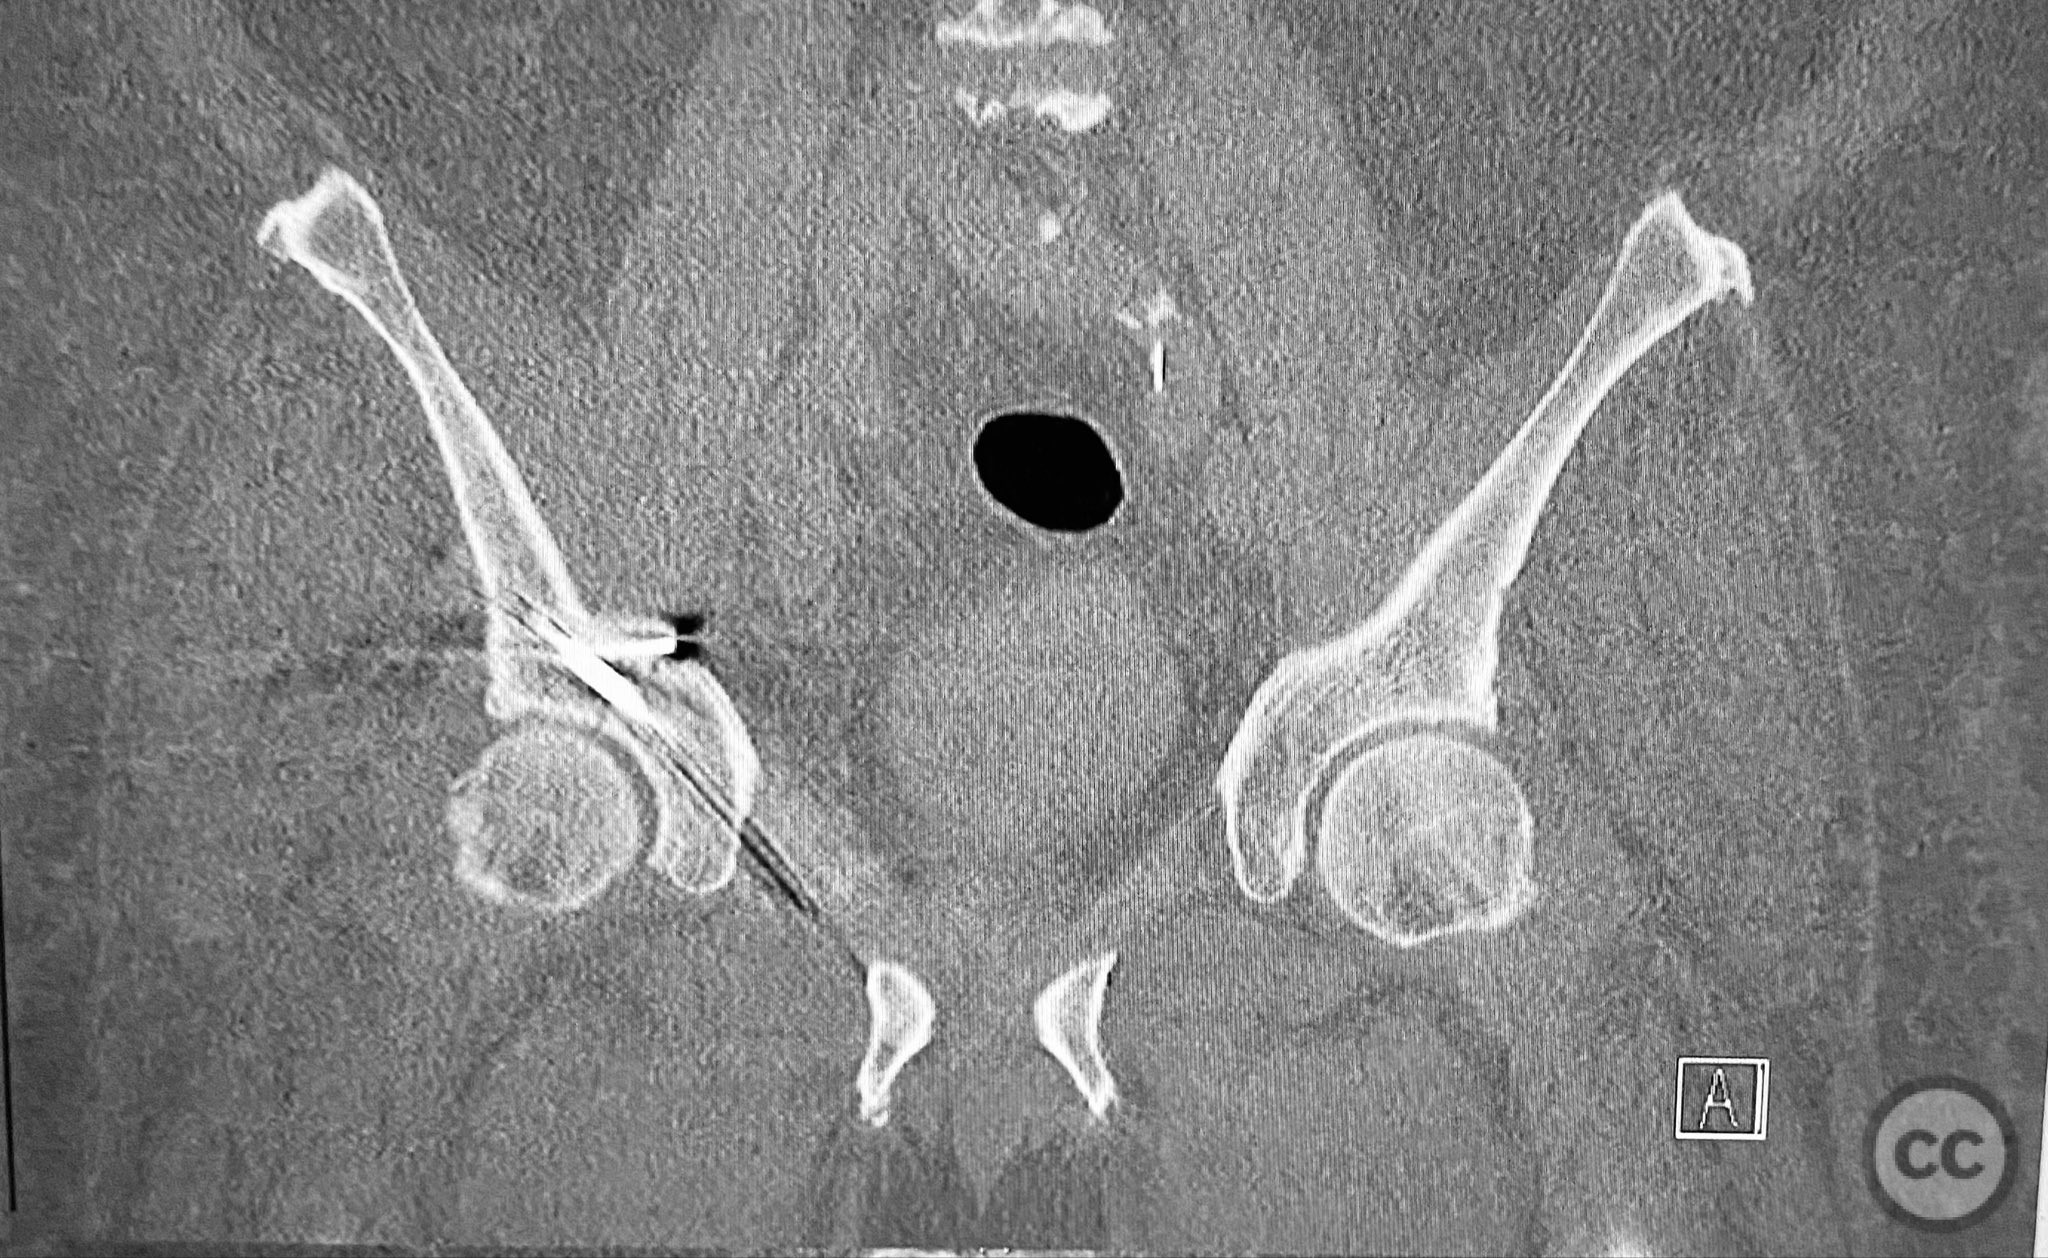

Clinical and radiological findings:  A 79-year-old male sustained a high-energy injury in a motor vehicle collision, resulting in a complex acetabular fracture-dislocation. Radiographs and computed tomography demonstrated a posterior wall and transverse acetabular fracture (AO/OTA 62-B1.3), with the posterior wall fragments displaying an atypical caudal hinge configuration. The medial wall fragment was non-articular. Axial imaging revealed an impacted osteochondral fragment obstructing reduction, as well as disruption of the capsular structures adjacent to the intact articular segment. The obturator internus tendon appeared taut but intact, with no evidence of sciatic nerve impingement or superior gluteal neurovascular compromise.

Anatomical surgical approach:  A standard Kocher-Langenbeck approach was performed, incising through the gluteal fascia and splitting the fibers of the gluteus maximus. The short external rotators were identified and protected, with subperiosteal dissection exposing the posterior column and wall of the acetabulum. The sciatic nerve was identified and mobilized laterally. The posterior capsule was found disrupted adjacent to the intact articular surface. The impacted osteochondral fragment was extracted from the joint space. The transverse fracture plane was debrided and reduced using clamps, with a greater trochanteric bone hook employed to manipulate the femoral head beneath the acetabular dome during reduction. Provisional fixation was achieved with a percutaneous lag screw across the transverse component. The peripheral posterior wall fragment was anatomically reduced and stabilized with a contoured plate. The medial wall defect provided access for reduction of the impacted articular segment, which was bone grafted prior to reduction and plating of the medial wall. Capsular tissues were repaired with nonabsorbable sutures prior to layered wound closure.

The posterior wall fragments exhibited an unusual caudal hinge morphology, necessitating careful mobilization to avoid propagation or comminution. Removal of the impacted intra-articular fragment was essential to achieve concentric reduction of the femoral head within the acetabular dome. Use of a greater trochanteric bone hook facilitated precise control of femoral head position during reduction maneuvers. The medial wall fragment, though non-articular, allowed direct visualization and accurate reduction of the impacted osteochondral segment, which was supported with bone graft prior to definitive fixation. Repair of disrupted capsular tissues was performed to restore soft tissue integrity and potentially reduce postoperative instability.

Orthopaedic implants used:   3.5mm pelvic reconstruction plate (posterior wall), 3.5mm pelvic reconstruction plate (medial wall), percutaneous cannulated lag screw, cancellous bone graft